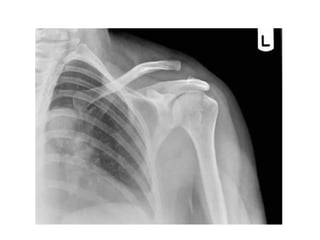

INCIDÊNCIAS OMBRO

Antero posterior –

rotação interna